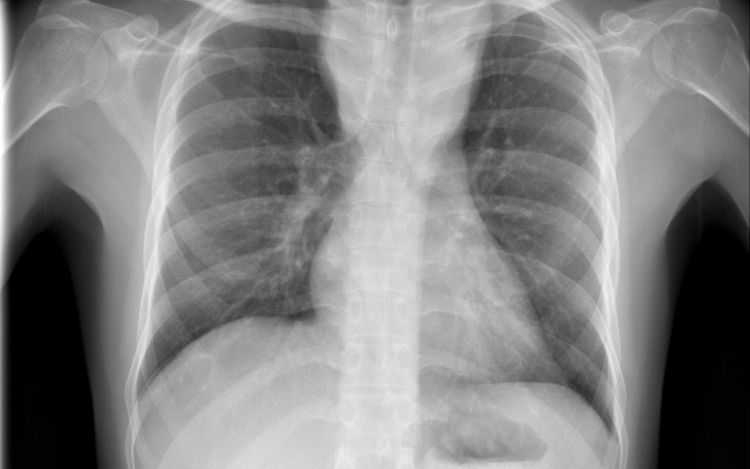

Hétfő reggel óta tbc-tesztet végeznek el a gyerekeken egy szatymazi általános iskolában, ahol egy hete fertőző tüdőbetegségben halt meg egy korábban ott dolgozó nő - közölték az M1 aktuális csatorna déli Híradójában.

A Délmagyar hírportál hétfő reggel írt arról, hogy februárig dolgozott a szatymazi iskolában közmunkásként az nő, aki tuberkulózisban (tbc) halt meg egy hete. Az ügyben rendkívüli szülői értekezletet tartottak. Az általános iskola 260 tanulója közül szülői beleegyezéssel 250-en végzik el a tbc-tesztet.

Az M1 tudósítója a helyszínről azt mondta: több szülővel beszéltek, ők nem voltak megriadva; elmondták, hogy az iskola azonnal tájékoztatta őket arról, mi történt a nővel, aki takarítóként dolgozott az iskolában február végéig. A tudósító megjegyezte, a tbc tüneteinek lappangási ideje 28-30 nap, ez az idő már letelt, de egyetlen gyereken sem tapasztaltak egyetlen tünetet sem.

Felidézték, hogy Magyarországon 1954 óta kötelező a tbc elleni védőoltás. Most az iskola diákjain biztonsági intézkedésként végzik el az úgynevezett Mantoux-tesztet, amely kimutatja, hogy védettek-e a tbc ellen. Ezt a tesztet később, három és hat nap múlva is megismétlik - hangzott el a Híradóban.

Április elején egy debreceni óvodában volt szükség hasonló intézkedésekre, mert az intézmény egyik dolgozója tüdőtuberkulózissal fertőződött meg.